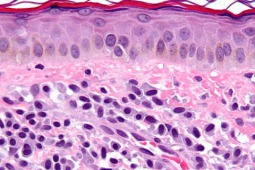

Mastocytoza jest heterogenną jednostką chorobową, u podłoża której leży klonalna proliferacja i gromadzenie się mastocytów w tkankach – najczęściej w skórze i szpiku kostnym. Postać ograniczona do skóry dominuje u dzieci, zaś mastocytoza układowa występuje u większości dorosłych. Choroba wiąże się z podwyższonym ryzykiem wystąpienia reakcji anafilaktycznej. Diagnozując mastocytozę, należy zadać pytanie – czy zmiany skórne rzeczywiście są mastocytozą skóry. W razie wątpliwości klinicznych w odpowiedzi na takie pytanie pomocne jest badanie histopatologiczne. Kolejna rzecz dotyczy tego, czy choroba jest ograniczona wyłącznie do skóry. Ekspert uczulała, iż nie należy poprzestawać na diagnostyce skóry. Znacząca rolę odgrywają następujące badania: morfologia z rozmazem, tryptaza oraz mutacja D816V genu KIT we krwi obwodowej. Dr hab. med. Magdalena Lange wśród trudnych pytań na jakie dermatolog natrafia podczas diagnostyki i leczenia pacjenta z mastocytozą wymieniła m.in.: jak interpretować wynik stężenia tryptazy mastocytowej w surowicy, jakie jest znaczenie diagnostyczne badania mutacji genu KIT we krwi obwodowej, co jest nowym trendem na świecie, jakie jest ryzyko wystąpienia reakcji anafilaktycznej u chorych na mastocytozę i jak można jej zapobiegać, jak przygotować chorego do zabiegu operacyjnego oraz jakie jest ryzyko rozwoju mastocytozy układowej u dzieci.